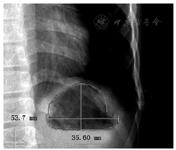

(1)检查方法:立位胸部平片检查体位采用后前位,摄片仪器为德国西门子DR机(Axiom Aristos VX),胸片拍摄条件为电压125 kV,1.26 mAs,胶片距1.8 m,自动调节曝光时间,在患者吸气后屏气时进行自动曝光。(2)结果判读:根据入选标准和排除标准将符合标准的初选病例的ID号和胸片拍摄日期分别提供给1名耳鼻喉科和1名消化科高年资主治医师,通过医院PACS系统(Synapse,FUJIFILM公司)调出胸片图像,调节窗宽、窗位,使胸片上的胃泡达到最佳的视觉效果,然后使用内置测量工具对胃泡高度、宽度以及面积进行测量(图1),测量前对两人进行判读标准的培训,且规定胸片上未见胃泡的病例以上三个测量数据均设为0(mm或mm2)。对两人认为存在间位结肠的原因导致胃泡无法准确测量的病例予以集中讨论后排除。取两者测量平均值纳入统计。

胃泡高度比较显示四组间差异有统计学意义(P=0.004),单纯立位阳性组、双体位阳性组和单纯卧位阳性组呈递减趋势,事后两两比较显示单纯立位组与单纯卧位组间差异有统计学意义(P=0.001),单纯立位组与对照组间差异有统计学意义(P=0.034);胃泡宽度和胃泡面积比较呈现同样趋势,但差异无统计学意义(P=0.340,P=0.186)(表2,图3)。